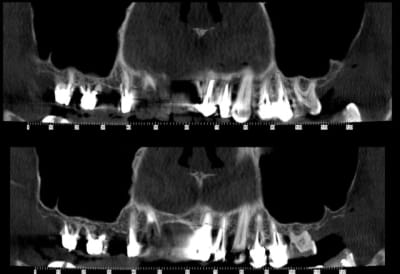

Bonjour, je sèche sur un cas, dont je vous joint le scan.

Je pensais m'en sortir avec des proth sur implants pour 13->11 et du classique par ailleurs.

Malheureusement, j'ai peu d'épaisseur osseuse en antérieur; j'ai par ailleurs peu d'expérience en greffe ou expansion : je n'en connais pas les limites et ne sais donc pas comment aborder mon cas...

Et une belle pano pour commencer

on a pas le scan des antérieures? où alors j'ai mal vu

Sur la 1ere planche, il y a qq reconstitutions pano des antérieures.